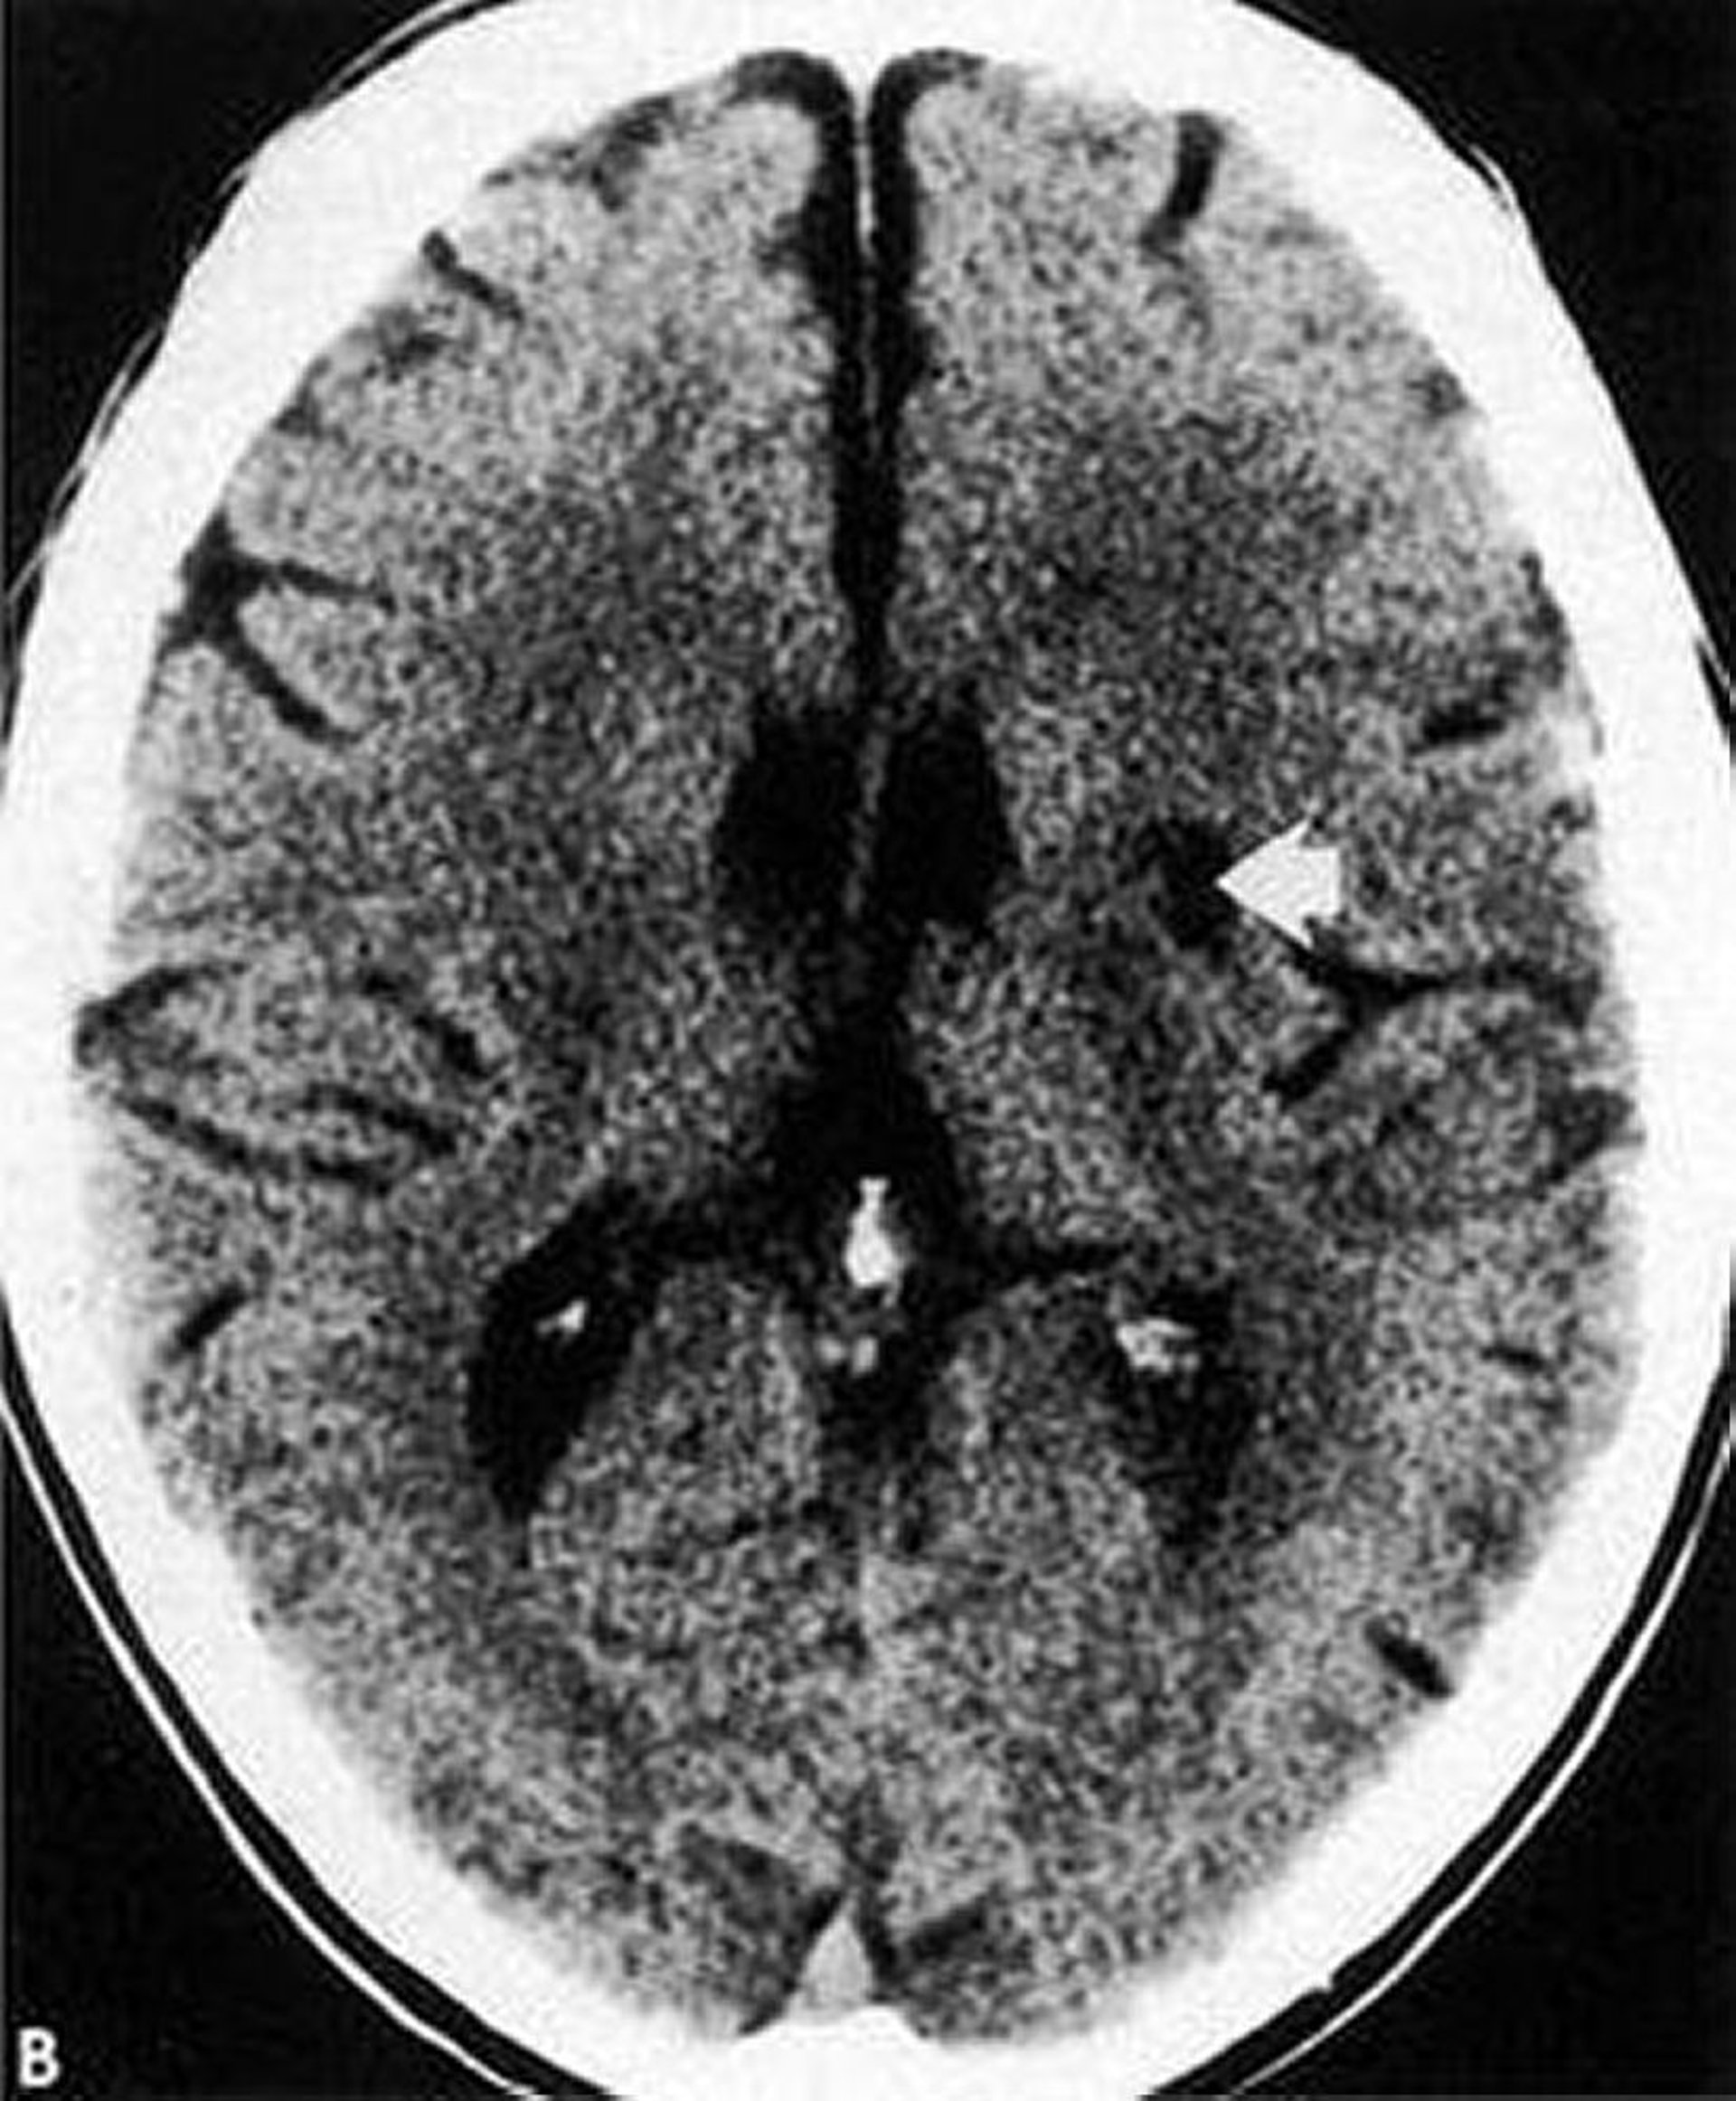

Questa scansione TC mostra un infarto lacunare (freccia) a bassa densità e ben definito all'interno dei gangli della base.

By permission of the publisher. From Geremia G, Greenlee W. In Atlas of Cerebrovascular Disease. Edited by PB Gorelick and MA Sloan. Philadelphia, Current Medicine, 1996.